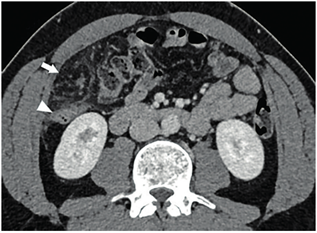

Ante la persistencia del dolor se decidió complementar los estudios con tomografía computarizada de abdomen con y sin contraste intravenoso (Figuras 1 y 2) donde se aprecia infarto del omento, para lo que se inicia tratamiento médico conservador. Luego de 24 horas aumenta el dolor abdominal, por lo que se realiza laparoscopia exploradora. En el intraoperatorio, se confirma necrosis del sector superior derecho del epiplón mayor; se realiza la resección con ligasure® (Figura 3). Tuvo buena evolución posoperatoria, dando de alta a las 48 horas. La anatomía patológica confirmó el diagnóstico de infarto omental.

Figura 1. Tomografía de abdomen con contraste en fase venosa, corte axial, donde se observa a nivel de flanco derecho una alteración en la densidad del epiplón mayor, bien delimitada por un halo hiperdenso (flecha). Contacta hacia atrás con el colon ascendente, el cual presenta paredes discretamente engrosadas, de aspecto inflamatorio, desproporcionadamente menor a la alteración del epiplón (punta de flecha).